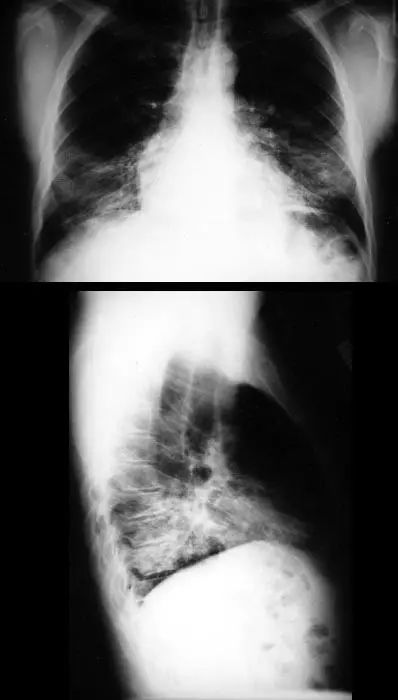

图1.1 细菌性肺炎。右上叶肺炎患者的放射影像。胸廓前后径增大,提示有慢性阻塞性肺疾病(COPD)。

图1.2 细菌性肺炎。双肺下叶肺炎患者影像。